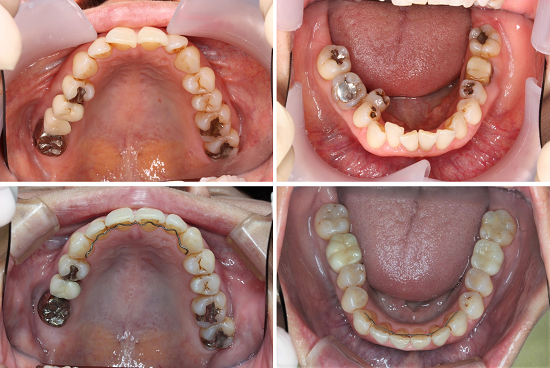

叢生(凸凹)の矯正治療例(50代女性)

叢生の矯正治療例

50代女性の患者様です。

歯が磨きにくいこと、歯と歯茎が痛いと来院されました。

ワイヤーをつけ歯並びの横幅を広げながら

歯の凸凹を改善し、歯磨きもしやすくなりました。

右上の歯が1本少なくなっているように見えますが

歯を抜いたのではなく

ブリッジのポンティック(人工の歯)を除去しています。

| 年齢・性別 | 50代女性 |

| 矯正治療期間 | 3年1か月 |

| 抜歯の有無 | 非抜歯 |

| 治療費 | 1,138,500円/税込(検査料、装置代、調整料含む) |

| リスク・注意点 | 歯の移動に伴い、痛みや違和感を感じる場合があります。 矯正治療後は、保定装置を装着しなければ歯が後戻りします。 |